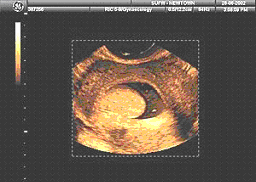

![]() 3D изображение на полипи на матката |

При пациентите, подложени на това изследване по повод стерилитет, често има вероятност за полипи в маточната кухина, което може да е причина за невъзможността за зачеване. Процедурата е особено важна при онези пациенти, на които предстоят IVF процедури, при които полипите на маточната кухина могат да доведат до неуспех.